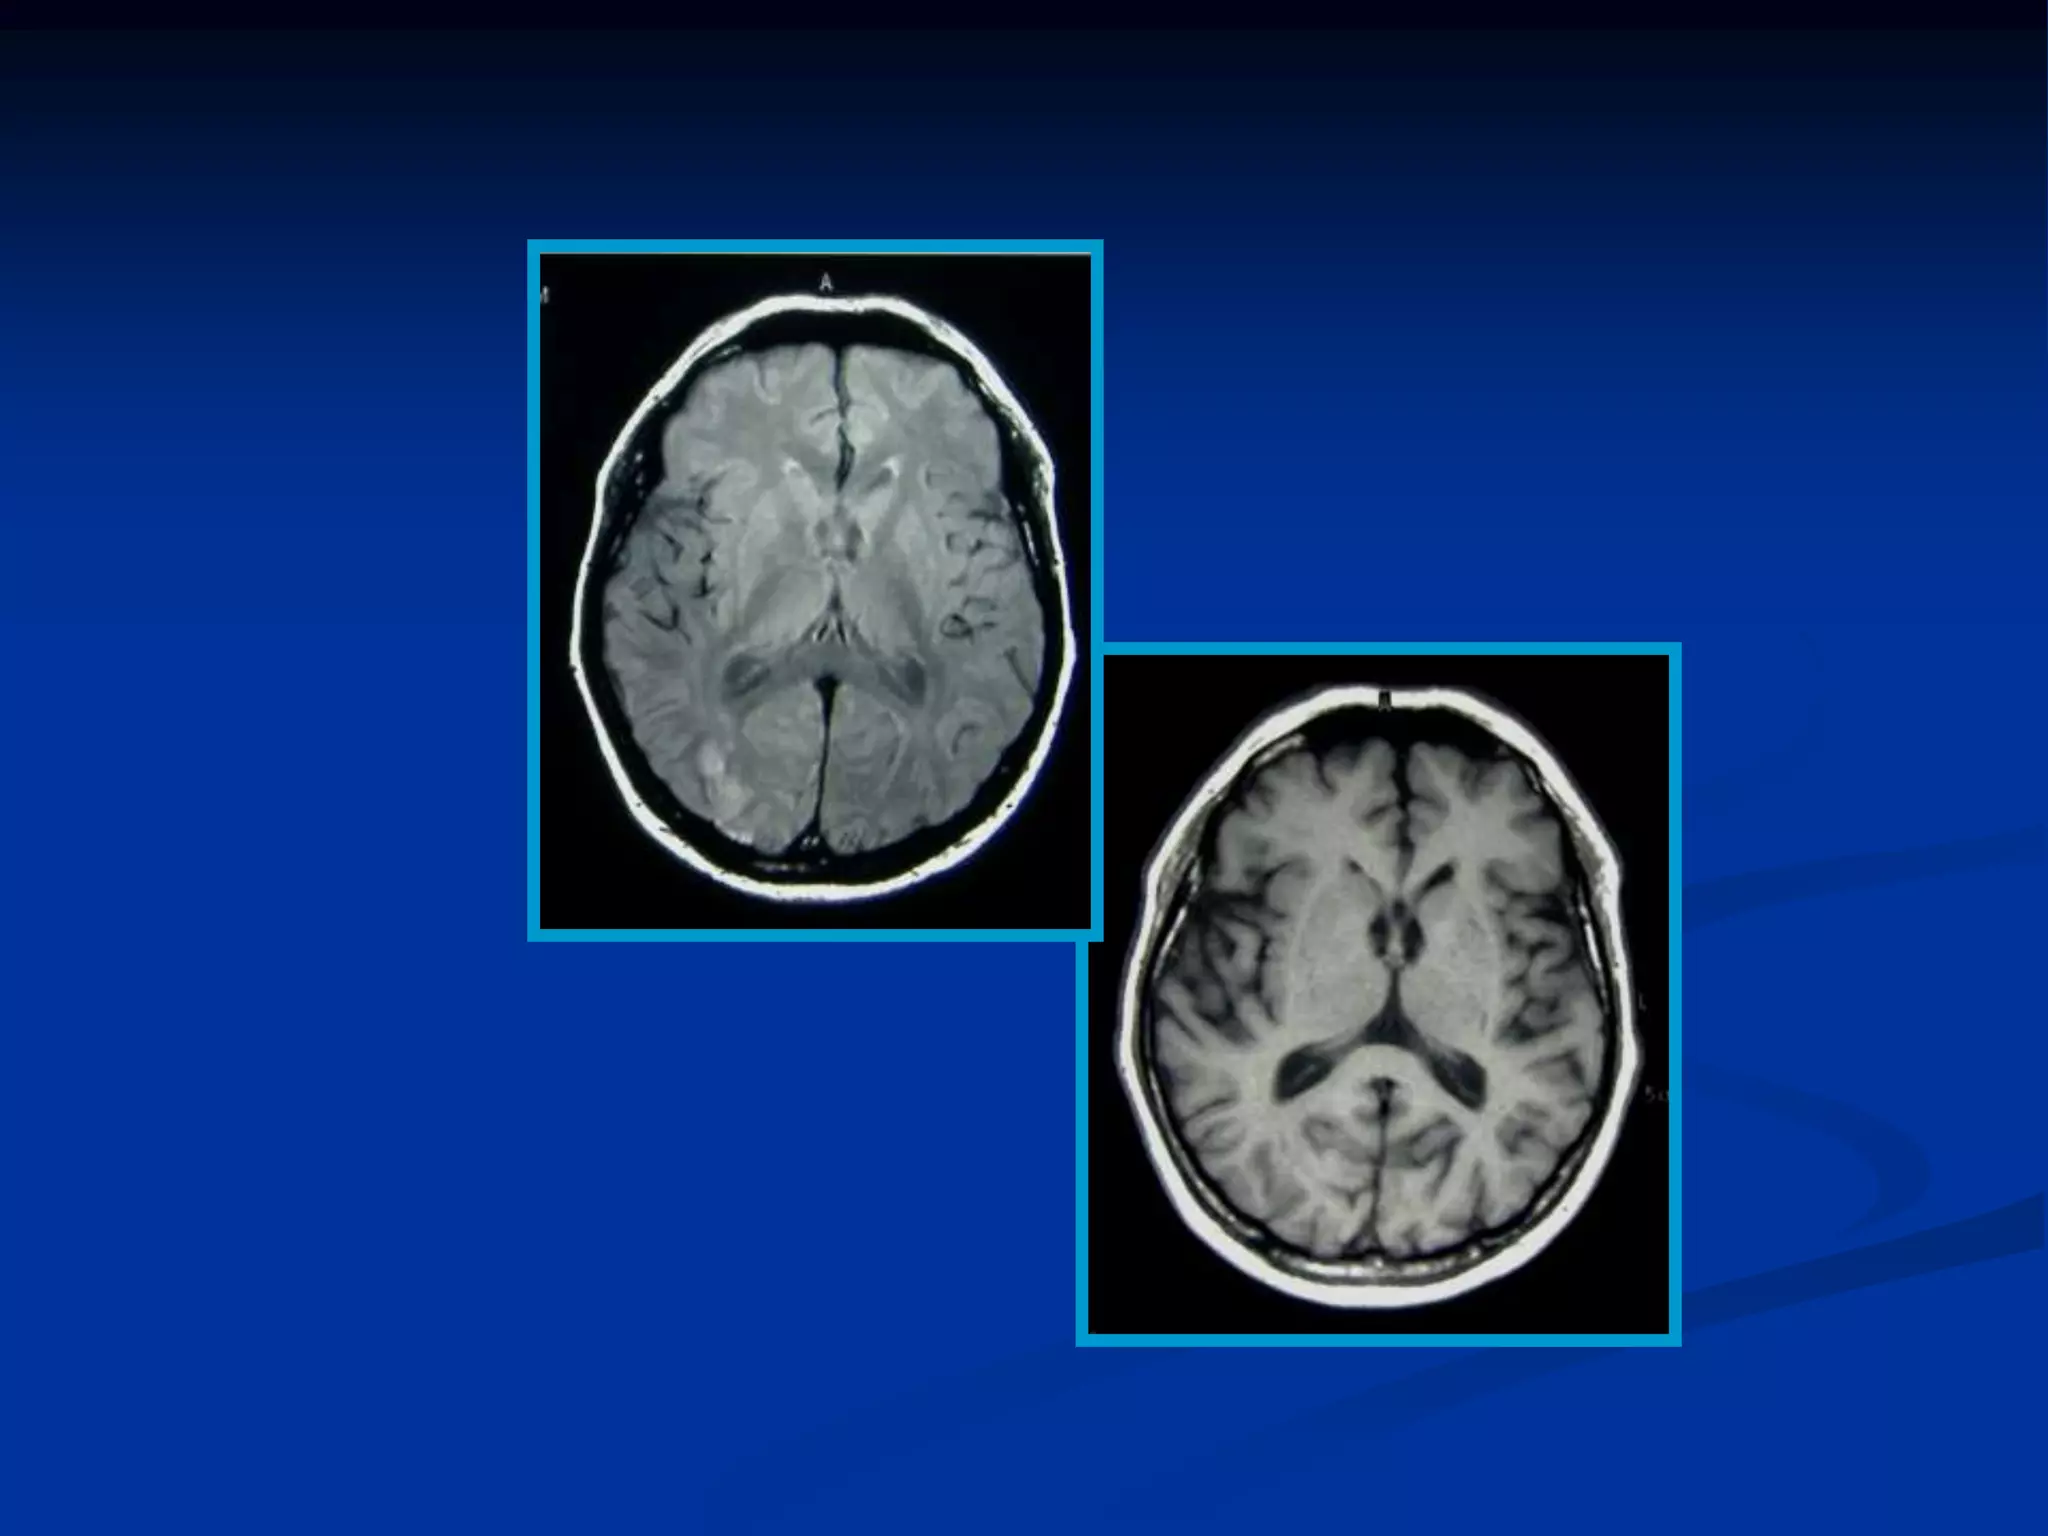

• En el cerebro el LCR, tiene un T1 largo y la señal es

hipointensa.

• La sustancia gris tiene menor intensidad de señal (agua)

que la sustancia blanca (grasa)

   En el cerebro un sangrado de cierto tiempo tiene un T2

corto porque sustancias de degradación de la sangre

(hemosiderina) produce heterogeneidades locales y

como consecuencia un desfase rápido de los

protones, poca señal que se ve oscura en la imagen

(hipointensa).